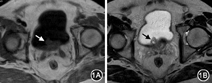

患者男,71岁。2009年11月因进行性排尿不畅10余年,排尿困难10 d入浙江大学绍兴医院就诊,临床诊断前列腺增生症,施行经尿道前列腺等离子切除术时发现尿道前列腺部肿物。入院体检:膀胱区叩浊,双肾区叩痛阴性。直肠指检:前列腺增生,中间沟变浅,质韧,无明显结节,无触痛。实验室检查:显微镜检查尿红细胞+/HP;总前列腺特异性抗原(PSA)1.662 μg/L(参考范围0~4.0 μg/L),游离前列腺特异抗原0.252 μg/L(参考范围0~0.934 μg/L),前列腺抗原比值0.155(参考范围0.2~0.5);肿瘤相关指标除铁蛋白升高328.8 μg/L(参考范围4.6~274.6 μg/L)外均正常。经直肠超声检查(TRUS)示:前列腺增大并钙化,前列腺内囊性结节。磁共振成像示尿道前列腺部肿物突入膀胱(图1)。术中见尿道前列腺部右侧叶近膀胱颈口处约2.0 cm×2.0 cm大小菜花状带蒂实性肿物,电切肿瘤并前列腺各叶。术后正电子发射计算机断层显像及肠镜检查未见胃肠道及其他肿瘤病灶。